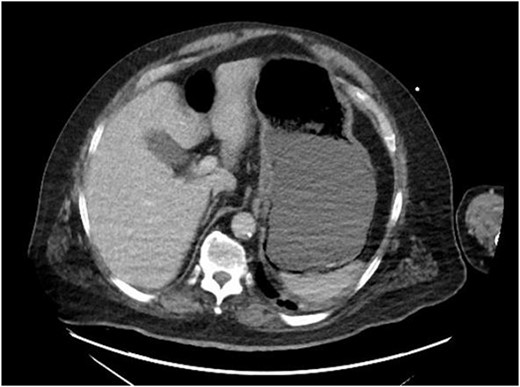

Repeat CT of the abdomen and pelvis: decompression of the stomach with persistent gastric pneumatosis.